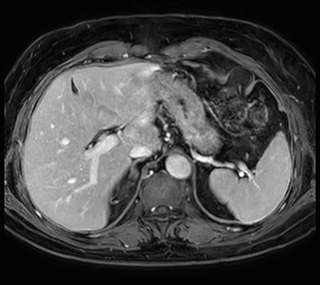

Excellent image quality is obtained in this dynamic scan., C-SENSE factor 5.4, scan time is 1:20 min, voxel size is 0.8 x 0.8 x 1.6 mm, Ingenia Ambition, 1.5T.

Cor 3D T2